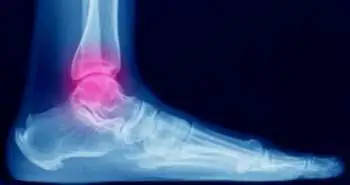

Supramalleolar osteotomy, in combination with an intra-articular osteotomy, shows promising results in reconstructing malunited medial impacted ankle fractures.

The malunited medial impacted ankle fractures with varus ankle deformity can be effectively treated using supramalleolar osteotomy when combined with an intra-articular osteotomy, an analysis of a retrospective study published in the Journal, Foot & Ankle International.

The patients who were reported to have medial impacted ankle fracture from January 2011 and December 2014 were selected. These patients were classified into four classes; type A fractures, type B fractures with the AO classification, 44A2 and 44B3 and went through the operation. The pain, clinical and radiographic outcomes were assessed using visual analog scale (VAS), the Olerud and Molander Scale, and the modified Takakura classification stage, respectively.

After the treatment, the tibial ankle surface (TAS) angle and talar tilt angle (TTA), the radiographic variables showed a significant difference from the baseline. However, no difference was noticed within the mean tibial lateral surface (TLS). The average Olerud and Molander Scale score and VAS also showed an improvement from the baseline. On the other hand, the modified Takakura classification stage reflected no difference from the baseline.

All the above-evaluated results indicated the considerable importance of supramalleolar osteotomy combined with an intra-articular osteotomy.